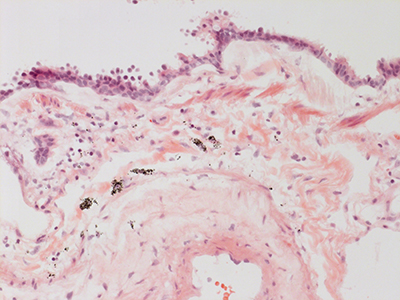

31 Year Old Adult Human Lung DD037 H&E